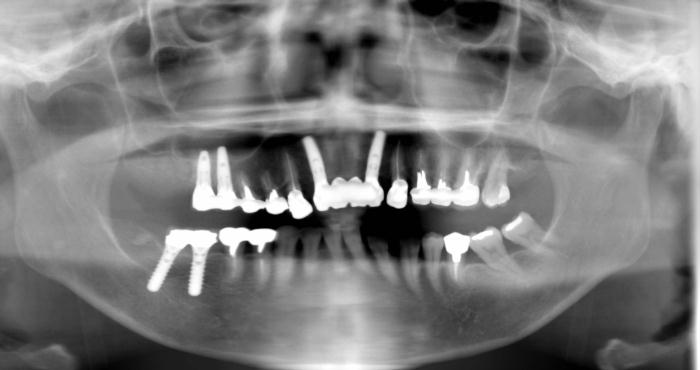

当院ではCTを院内に設置しておりますので、大学病院などに撮影に行くことはありません。

CTは、レントゲンではわからない骨や神経の位置や状態を把握することが可能で、安全なインプラント手術を行うことが可能です。

インプラント治療は、歯が抜けてしまった部分に人工歯根を埋入し人工歯をかぶせる治療法です。

インプラント本体は手術によって顎骨に埋め込みますが、顎の骨としっかりと結合・固定されるため、健康な自分の歯のようにしっかりと噛むことができるように機能性が回復します。

インプラント治療は、失った歯が1本から数本のケース、全歯が無く総入れ歯が合わないようなケースなどに対応しております。

また、4~6本のインプラント本体を埋め込み、インプラント専用の義歯を固定する治療も可能です。